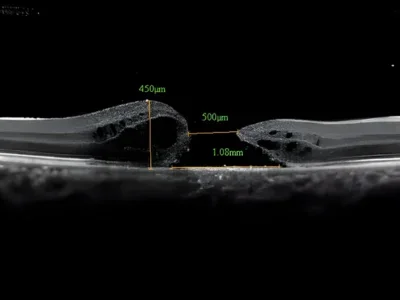

A detailed OCT scan and dilated fundus examination assess the size, stage, and duration of the macular hole. This guides the surgical plan and helps set realistic visual expectations for recovery.

High-Resolution OCT Diagnostics

State-of-the-art optical coherence tomography allows us to map your macula in extraordinary detail, enabling precise surgical planning.